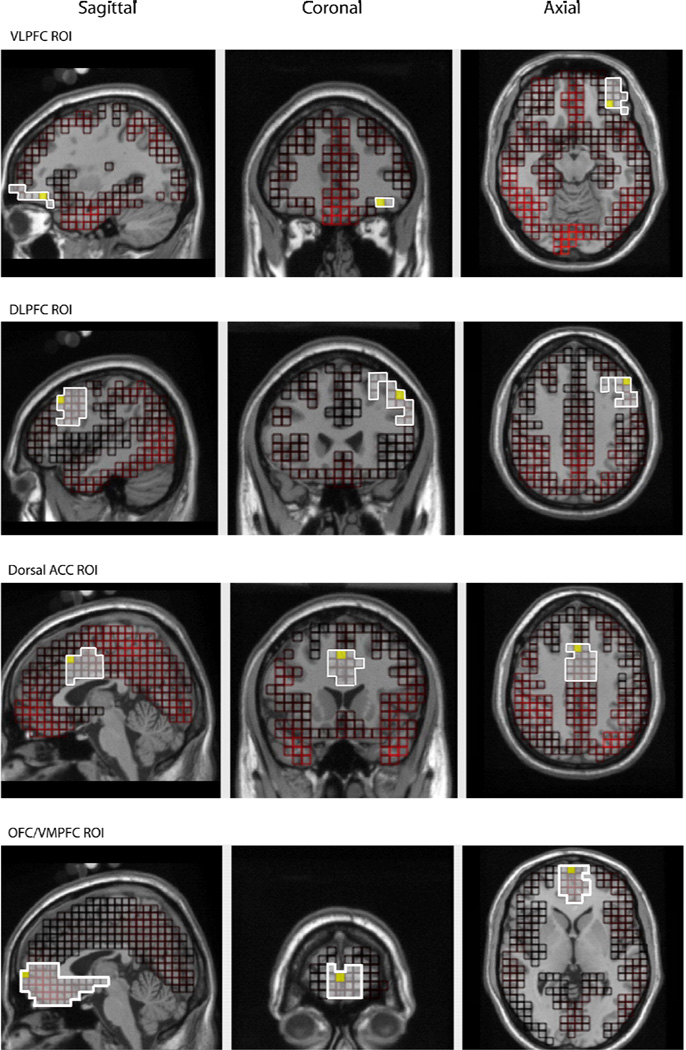

After the inverse model was applied to the entire cortex (2447 voxels), data were exported for morphology-based regions of interest (ROIs), generated using the Montreal Neurological Institute (MNI) average adult MRI. We were interested in four ROIs: dorsal ACC, DLPFC, VLPFC, and VMPFC (see Figure 2). Source waveform amplitudes (nA) for all voxels within an ROI were extracted and the voxel that showed the most activation for each ROI was analyzed.

Figure 2.

Morphology-based regions of interest (ROIs) generated using the Montreal Neurological Institute (MNI) average adult MRI.